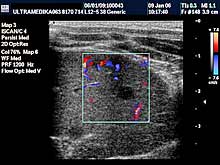

- Testisi

Pregled testisa, bez obzira da li postoji bol ili sumnja na

zapaljenje su apsolutna indikacija za pregled. Ultrazvučna

dijagnostika testisa može otkriti i zloćudni tumor testisa kod

mladih ljudi kod kojih su testisi normalnih karakteristika nakon

kliničkog pregleda pipanjem od strane lekara. Ultrazvučna rana

dijagnostika je osnovni preduslov za uspešno lečenje. Otkrivanje

proširenih vena testisa i nakon toga hirurška intervencija

sprečavaju pojavu smanjene proizvodnje spermatozoida.